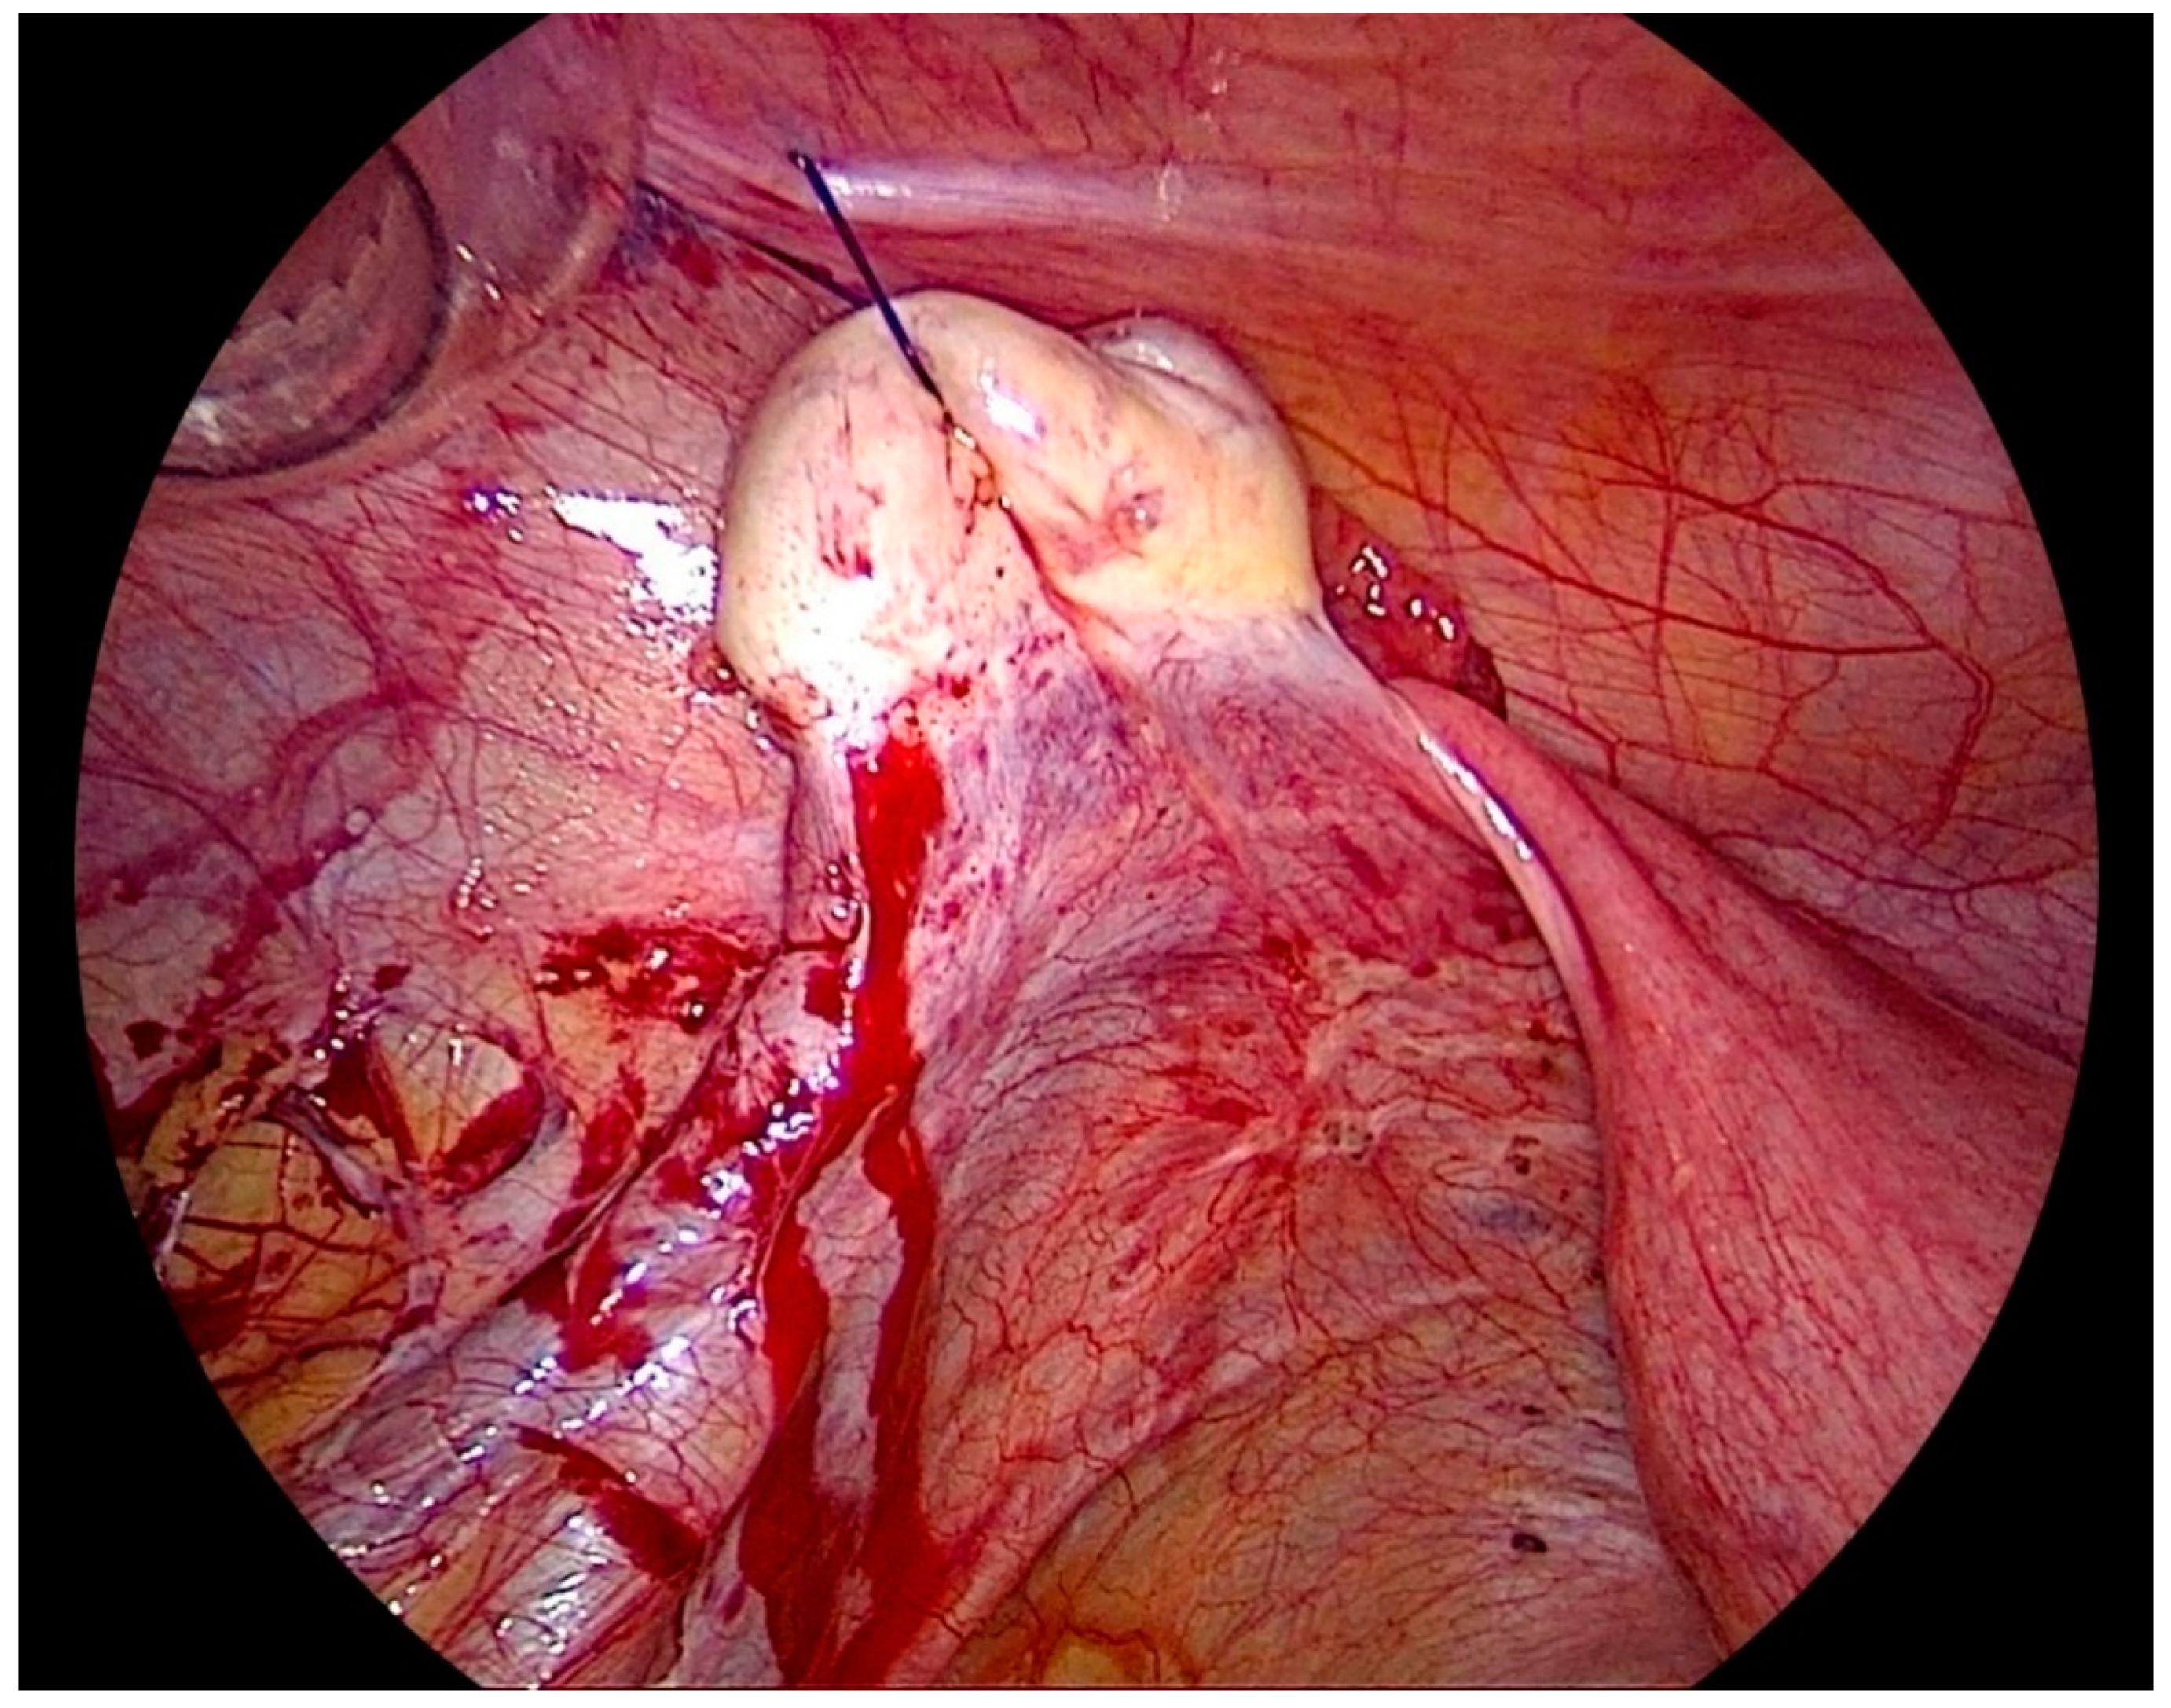

After the procedure is complete, the ovarian suspension is loosened to maintain a gap of 1–2 cm between the ovary and the abdominal wall to prevent adhesions. This suspension is maintained for 5 days, and sutures are cut on the day 5th-day post-surgery (Figure 3).

Figure 3. Left side ovary suspended to the anterior abdominal wall, with dissection of the left lateral pelvic wall.

Another illustration after endometriosis resection with the important anatomical structures shown (Figure 4). Vessels in the abdominal wall have to be kept in mind before doing an ovariopexy to prevent puncture of it [29]. Comfortable access to the lateral pelvic wall is really important to prevent damage to major structures like the ureter and uterine artery, a very common site for superficial and deep endometriosis.